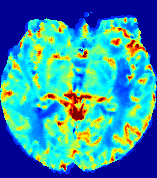

LesionRefer to captionRefer to captionRefer to captionRefer to captionRefer to captionRefer to caption𝐕rgbsubscript𝐕𝑟𝑔𝑏{\bf{V}}_{rgb}Refer to captionRefer to captionRefer to captionRefer to captionRefer to captionRefer to caption𝐕2subscriptnorm𝐕2{\|\bf{V}}\|_{2}Refer to captionRefer to captionRefer to captionRefer to captionRefer to captionRefer to captionRefer to caption3.53.53.52.82.82.82.12.12.11.41.41.40.70.70.70.00.00.0(mm/s)𝑚𝑚𝑠(mm/s)D𝐷DRefer to captionRefer to captionRefer to captionRefer to captionRefer to captionRefer to captionRefer to caption0.0200.0200.0200.0160.0160.0160.0120.0120.0120.0080.0080.0080.0040.0040.0040.0000.0000.000(mm2/s)𝑚superscript𝑚2𝑠(mm^{2}/s)Slice #1Slice #2Slice #3Slice #4Slice #5Slice #6

Figure 4: PIANO feature maps for another patient in the ISLES 2017 training set, where the lesion is located in the right hemisphere. Top row: segmented stroke lesion region (white) on different slices. The corresponding slices for the PIANO feature maps are shown in the following rows.

For a better insight into an estimated velocity field 𝐕𝐕{\bf{V}} and diffusion field 𝐃𝐃{\bf{D}}, we compute the following maps: (1) 𝐕rgbsubscript𝐕𝑟𝑔𝑏{\bf{V}}_{rgb}: Color-coded orientation map of 𝐕=(Vx,Vy,Vz)T𝐕superscriptsuperscript𝑉𝑥superscript𝑉𝑦superscript𝑉𝑧𝑇{\bf{V}}=(V^{x},V^{y},V^{z})^{T}, obtained by normalizing 𝐕𝐕{\bf{V}} to unit length and mapping its 3 components to red, green, blue respectively; (2) 𝐕2subscriptnorm𝐕2\|{\bf{V}}\|_{2}: 222 norm of 𝐕𝐕{\bf{V}}; (3) D𝐷D: scalar field in Eq. 5.

Fig. 3 and Fig. 4 show the PIANO feature maps estimated from two ISLES 2017 patients: all are highly consistent with the lesion in both cases. Details of the blood flow trajectories are revealed in 𝐕rgbsubscript𝐕𝑟𝑔𝑏{\bf{V}}_{rgb} by the ridged patterns and the sharp changes of colors in the unaffected (right) hemisphere, while the flat patterns appearing within the lesion provide little directional information about the velocity and indicate low velocity magnitudes. Velocity magnitudes are more directly visualized via 𝐕2subscriptnorm𝐕2\|{\bf{V}}\|_{2}, from which one can easily locate the lesion where 𝐕2subscriptnorm𝐕2\|{\bf{V}}\|_{2} is low. D𝐷D also indicates lower diffusion values in the lesion, though with less contrast potentially due to the fact that it captures the accumulated effect of CA diffusion at the voxel-level.